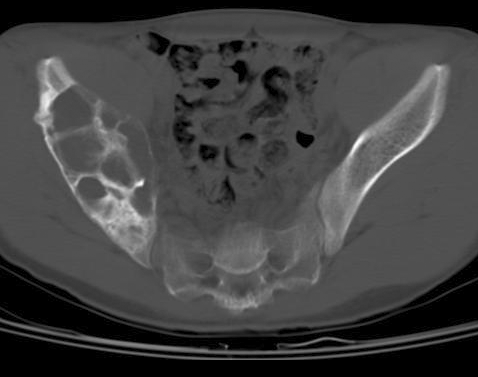

▌膨胀性破坏

膨胀性破坏是地图样破坏的特殊形式,影像学表现为骨质破坏区骨膨胀,周围可见不同程度扩张的骨壳(图 5、图 6、图 7、图 8)。膨胀性破坏是由于肿瘤从骨皮质内面破坏,骨外膜增生形成新生骨造成膨胀的。引起膨胀性破坏见于大多数良性肿瘤和肿瘤样病变如单纯性骨囊肿,动脉瘤样骨囊肿、内生软骨瘤和软骨粘液纤维瘤等,少数也可见于恶性肿瘤如转移瘤、骨髓瘤等。

图 6.膨胀性破坏:骨巨细胞瘤